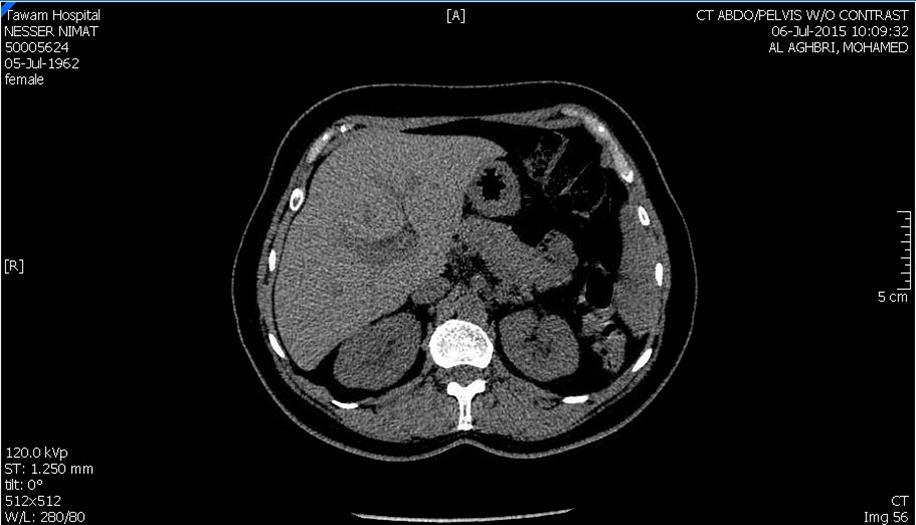

Blood tests on April 14th showed: Na = 131, K = 5.1, Urea = 6.9, S. Creatinine = 96, and eGFR = 61ml/min. Urine analysis and cultures confirmed E. coli urosepsis, blood cultures were negative. Renal US revealed echogenic kidneys, mild bilateral hydronephrosis of about 12 mm with normal ureters and urinary bladder (Figure 1 and Figure 2). Treatment with oral antibiotics resulted in improvement of temperature and dysuria. On April 20th patient seen by endocrinology and nephrology because of persistent back pain, dapagliflozin was discontinued and followed by resolution of symptoms in few days. Patient had two kidney ultrasounds in May and June, both indicated gradual resolution of bilateral hydronephrosis. Repeat CT of the abdomen on July 7th revealed complete resolution of hydronephrosis (Figure 3). Most recent eGFR is 72 ml/min.

Figure 3.CT Scan showing bilateral kidneys with no hydronephrosis